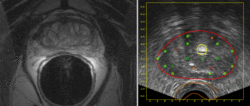

MR-US registration

• Prostate contouring in MRI guided biopsy (abstract)

Siddharth Vikala, Steven Hakerb, Clare Tempanyb, Gabor Fichtingera,(a) Queen’s University, Kingston, ON, Canada , (b) Brigham & Women’s Hospital, Boston, MA, USA